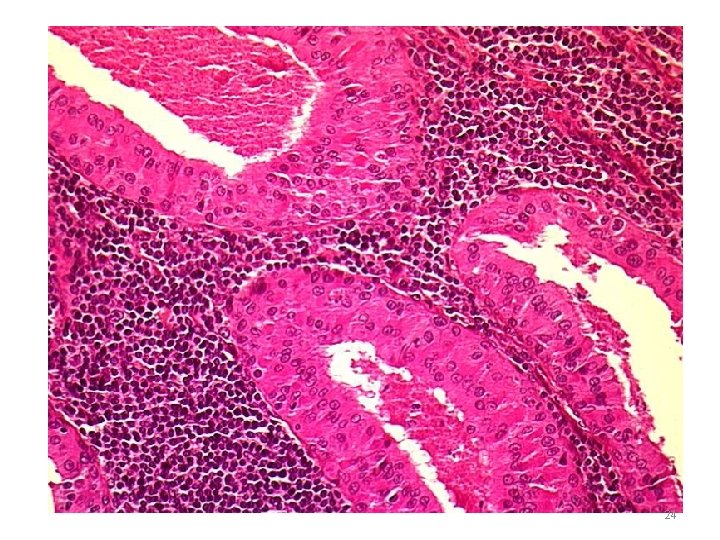

WARTHIN’S TUMOUR Microscopy Cystic spaces - Narrow / cleft-like CYSTADENOMA Lining – double-layered epithelium – infoldings PAPILLARY • Inner (lumen) – palisade of columnar cells with abundant finely granular eosinophilic cytoplasm (oncocytic) • Outer (below the first) – cuboidal / polygonal Stroma - dense lymphoid tissue (germinal centres + ) LYMPHOMATOSUM 22

24